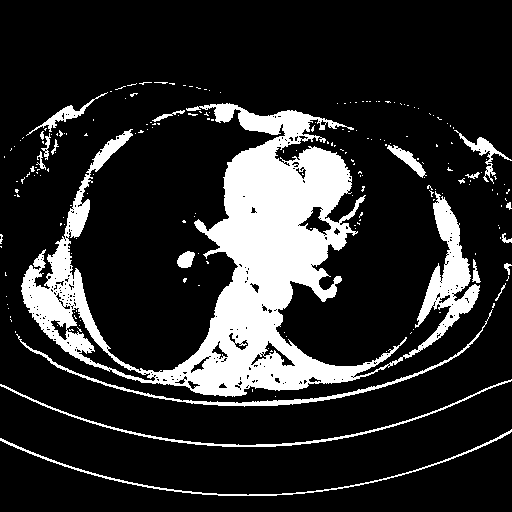

Original NATIVE CT scan (input)

Full window (WL 1023.5, WW 4095 β†’ Low βˆ’1024, High +3071)

Actual HU range: [-1024.0, 3071.0]